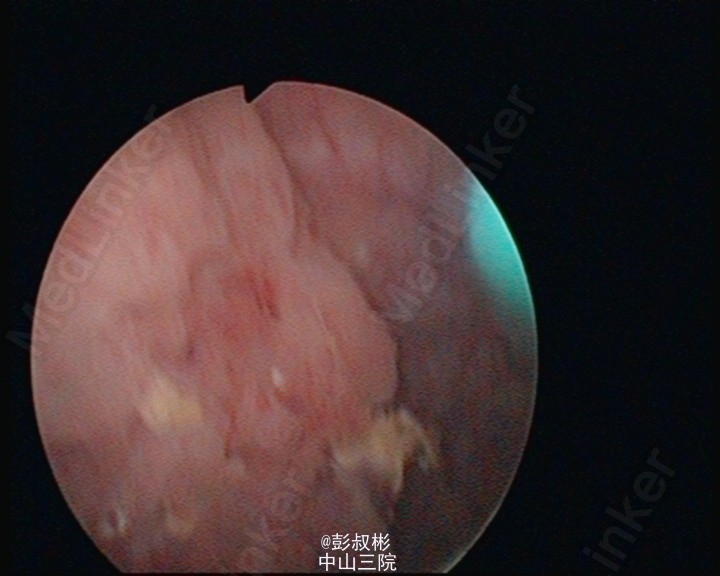

看看那些水草,水。。草。。样子